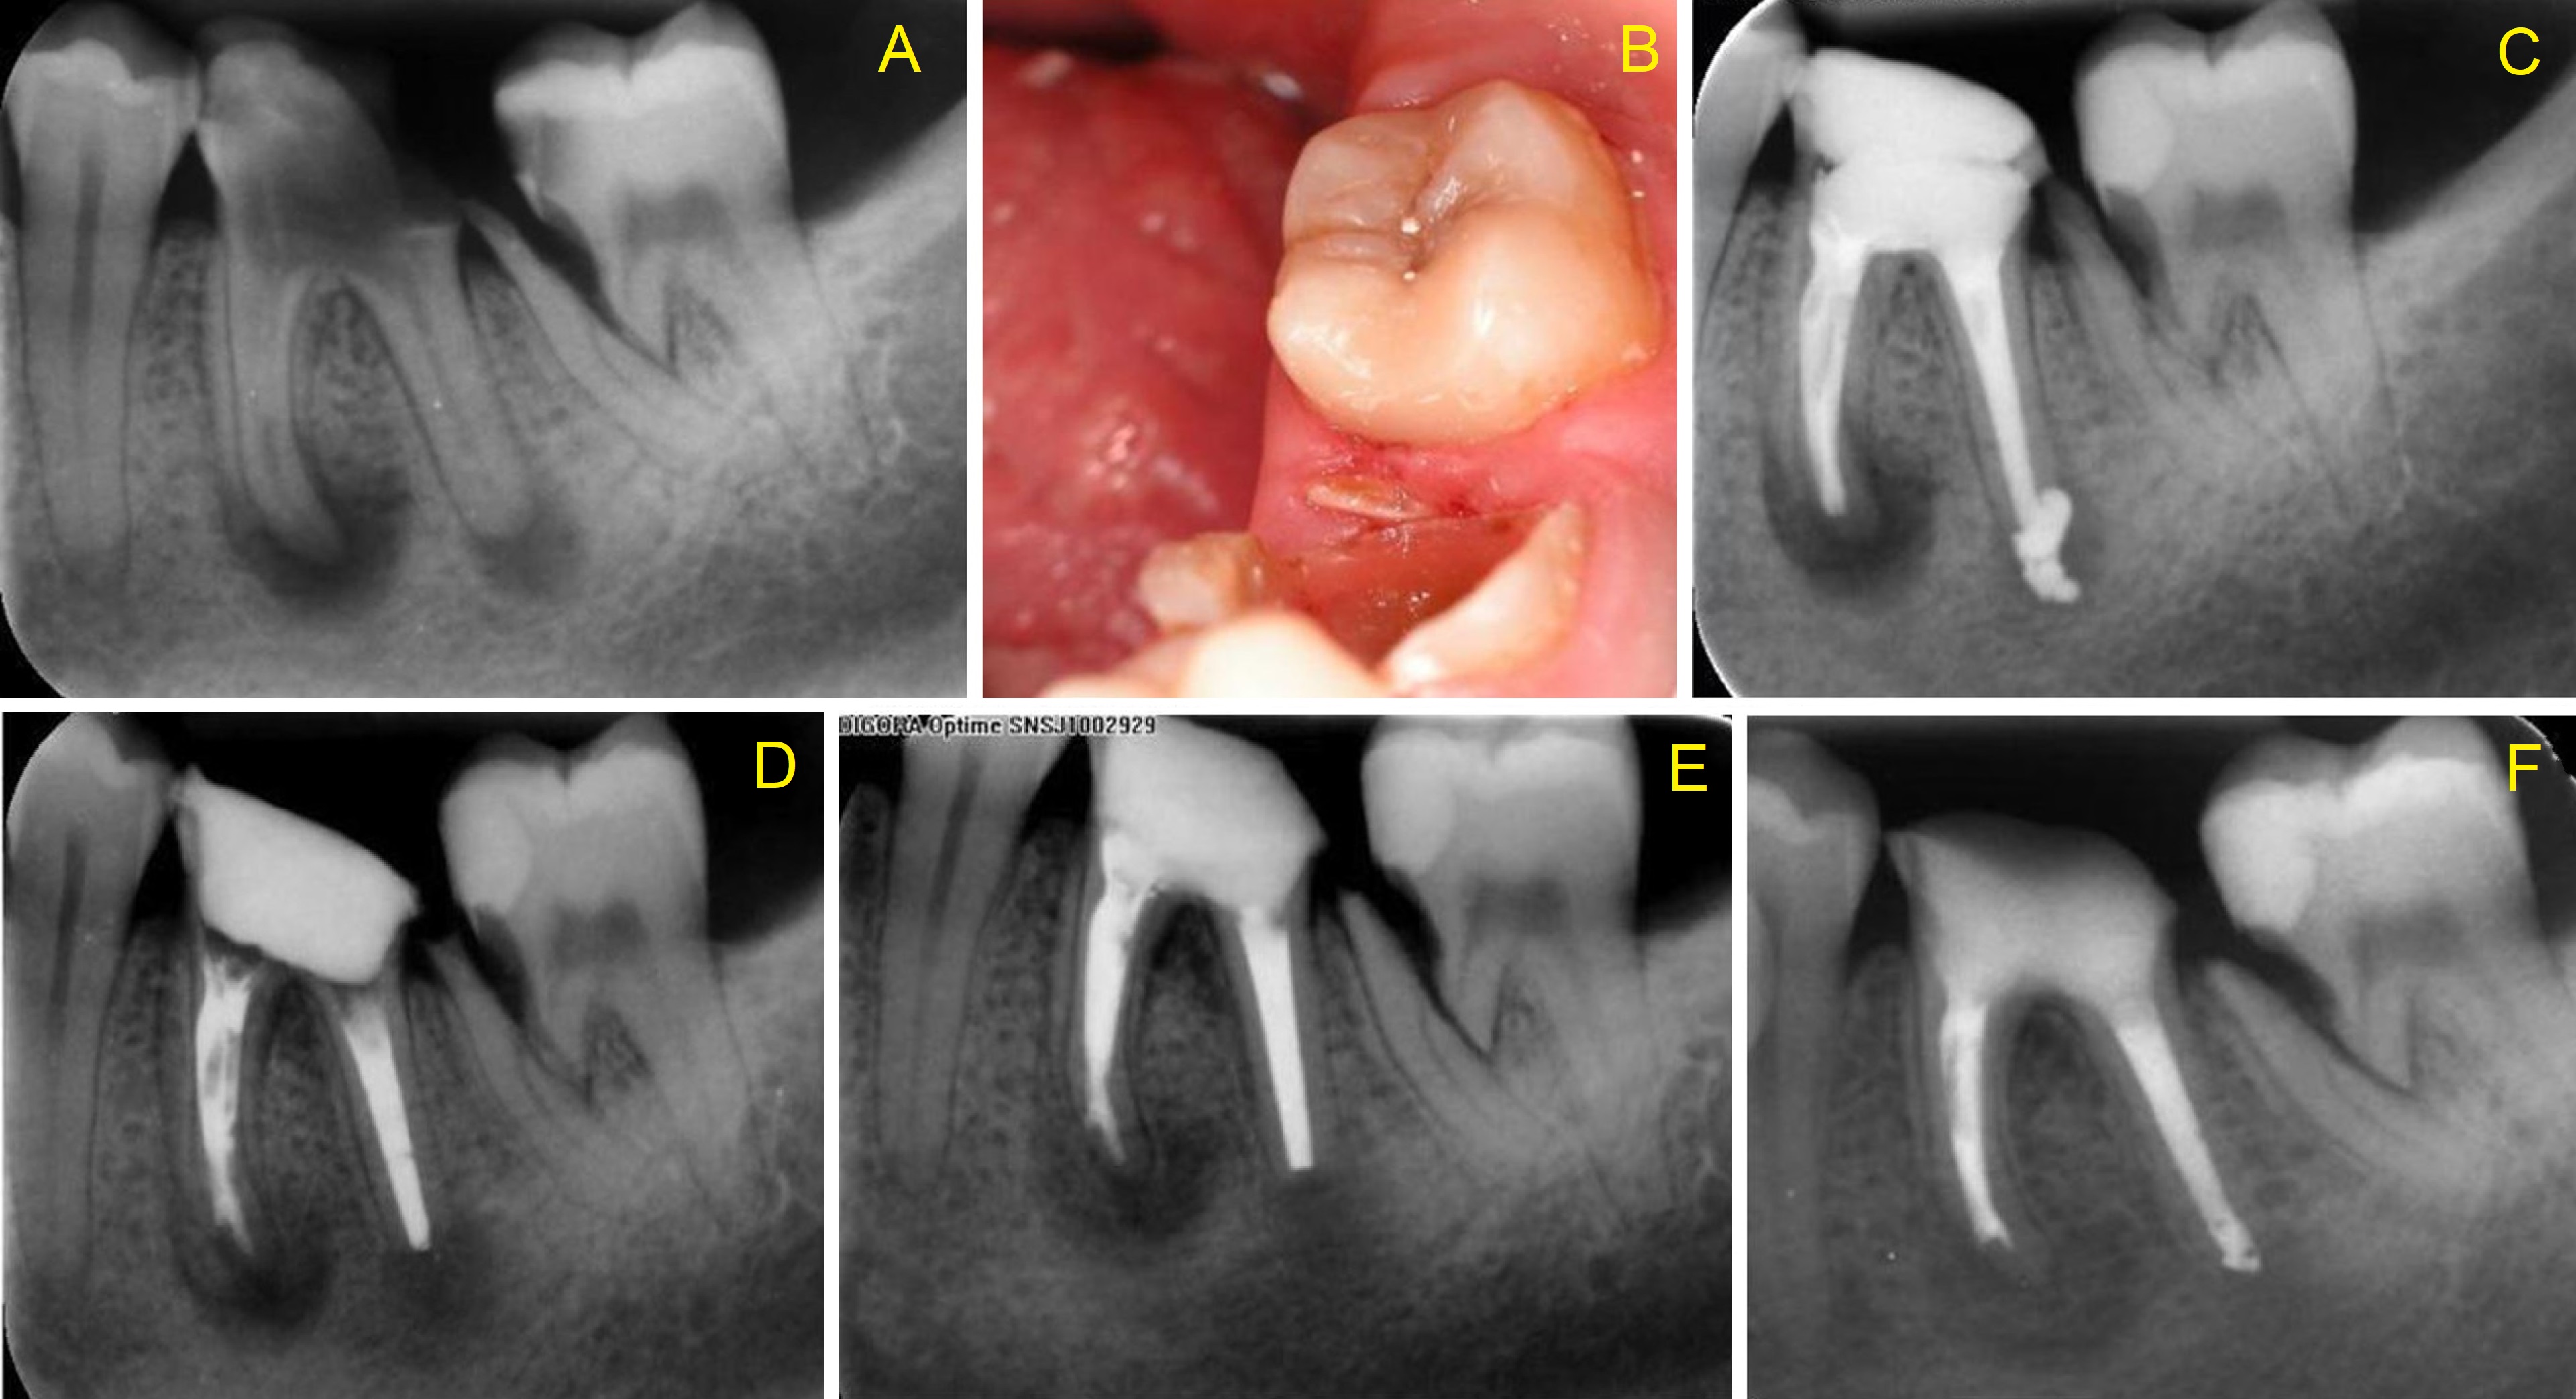

An oblique crown-root fracture was detected incidentally in the cervical middle third of the mesial root of a non-endodontically treated second lower right molar. Because the tooth was asymptomatic, the pulp responded positively to testing and no periapical pathosis was detected, an endodontic treatment was not indicated. Considering the unusual condition of tooth 47, substantial efforts were made to save tooth 46, which had been extensively destroyed by caries. A control cone beam computed tomography (CBCT) acquired 12 months after completion of the endodontic treatment of tooth 46 revealed almost complete resolution of the periapical pathosis in the first right molar, no changes in the fracture line and no periradicular radiolucency in the second right molar. The loss of this tooth could have resulted in postextraction atrophy of the alveolar bone and loss of support for the fractured root of the adjacent tooth.